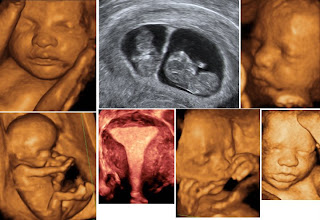

· Tüm batın, üriner sistem, pelvik, troid ultrasonlarına ek olarak gebelerde 2. Düzey ayrıntılı ultrason, gebelik ultrasonu, 4 boyutlu ultrason çekimleri.

· Tüm batın, üriner sistem, pelvik, troid ultrasonlarına ek olarak gebelerde 2. Düzey ayrıntılı ultrason, gebelik ultrasonu, 4 boyutlu ultrason çekimleri.

- Tüm batın, üriner sistem, pelvik, troid ultrasonlarına ek olarak gebelerde 2. Düzey ultrason, gebelik ultrasonu, 4 boyutlu ultrason çekimleri,

ULTRASON US USG ULTRASONOGRAFİYüksek frekanslı ses ( ultrasound ) dalgalarının farklı yoğunluktaki doku yüzeylerinden yansıması ile iç organların görüntülenmesidir.Yumuşak doku patolojilerinin incelenmesinde ve organların sınırlarının belirlenmesinde kullanılan bir yöntemdir. Sıvılarda yansıma olmadığından kistik yapılar solid yapılardan kolayca ayrılabilirler.İç organ patolojilerinin tespitinde hastayı rahatsız etmeden kolay uygulanabilen noninvaziv bir yöntem olması nedeniyle tercih edilmektedir.Ultrason öncesinde ön hazırlık gerebilir. Bu nedenle randevu alınması ve randevu sırasında verilecek bilgilere dikkat edilmesi önemlidir.OBSTETRİK GEBELİKTE ULTRASONBebeğin sayısı, geliş şekli, duruş şekli, anatomik yapısı, plasenta yerleşimi, amnion sıvı miktarı, gebelik yaşı, annedeki pelvik kitlelerin değerlendirilmesi için kullanılan en iyi yöntemdir. Ultrasonografinin bebek üzerinde şimdiye kadar kanıtlanmış bir yan etkisi bildirilmemiştir. Bilakis günümüzde gebelik takibinde güvenilir yöntemlerden biridir.- Erken gebelikte gebeliğin normal olup olmadığını ( dış gebelik, çoğul gebelik, mol, bozulmuş gebelik,...), gebelik yaşını saptamak için,

4 BOYUTLU ULTRASON4 boyutlu ultrasonografi klasik 2 boyutlu ultrasonografi kullanımını gereksiz kılacak ölçüde bir yöntem değildir. Her ikisinin de avantajlı olduğu üstünlükleri vardır. Örneğin, yarık damak ve dudak anomalilerinin saptanmasında, kol ve bacaklardaki bazı detay anomalilerin görülmesinde, nöral tüp defektlerinde 4 boyutlu ultrasonografi daha detaylı bilgi verebilmektedir. Buna karşın 2 boyutlu ultrasonografi bebeğin iç organlarını değerlendirmede hala 4 boyutlu ultrasonografiden üstündür.4 boyutlu ultrasonografi ile anne ve baba adayları doğmamış bebeklerinin gerçek görünümü ile normalde doğumdan sonra kurulması beklenen duygusal bağlarını daha önceden oluşturmaktadırlar.Görüntüler video formatında CD'ye kaydedip korunabilmektedir.Aynı zamanda canlı DVD kayıtlar ile evinde DVD de seyreder formatta kayıtlar verilmektedir. Ortalama 5-7 dakika kayıtlar birden fazla takipler yapılmaktadır.

· Tüm batın, üriner sistem, pelvik, troid ultrasonlarına ek olarak gebelerde 2. Düzey ayrıntılı ultrason, gebelik ultrasonu, 4 boyutlu ultrason çekimleri.

· Tüm batın, üriner sistem, pelvik, troid ultrasonlarına ek olarak gebelerde 2. Düzey ayrıntılı ultrason, gebelik ultrasonu, 4 boyutlu ultrason çekimleri.

· Tüm batın, üriner sistem, pelvik, troid ultrasonlarına ek olarak gebelerde 2. Düzey ayrıntılı ultrason, gebelik ultrasonu, 4 boyutlu ultrason çekimleri.

· Tüm batın, üriner sistem, pelvik, troid ultrasonlarına ek olarak gebelerde 2. Düzey ayrıntılı ultrason, gebelik ultrasonu, 4 boyutlu ultrason çekimleri.